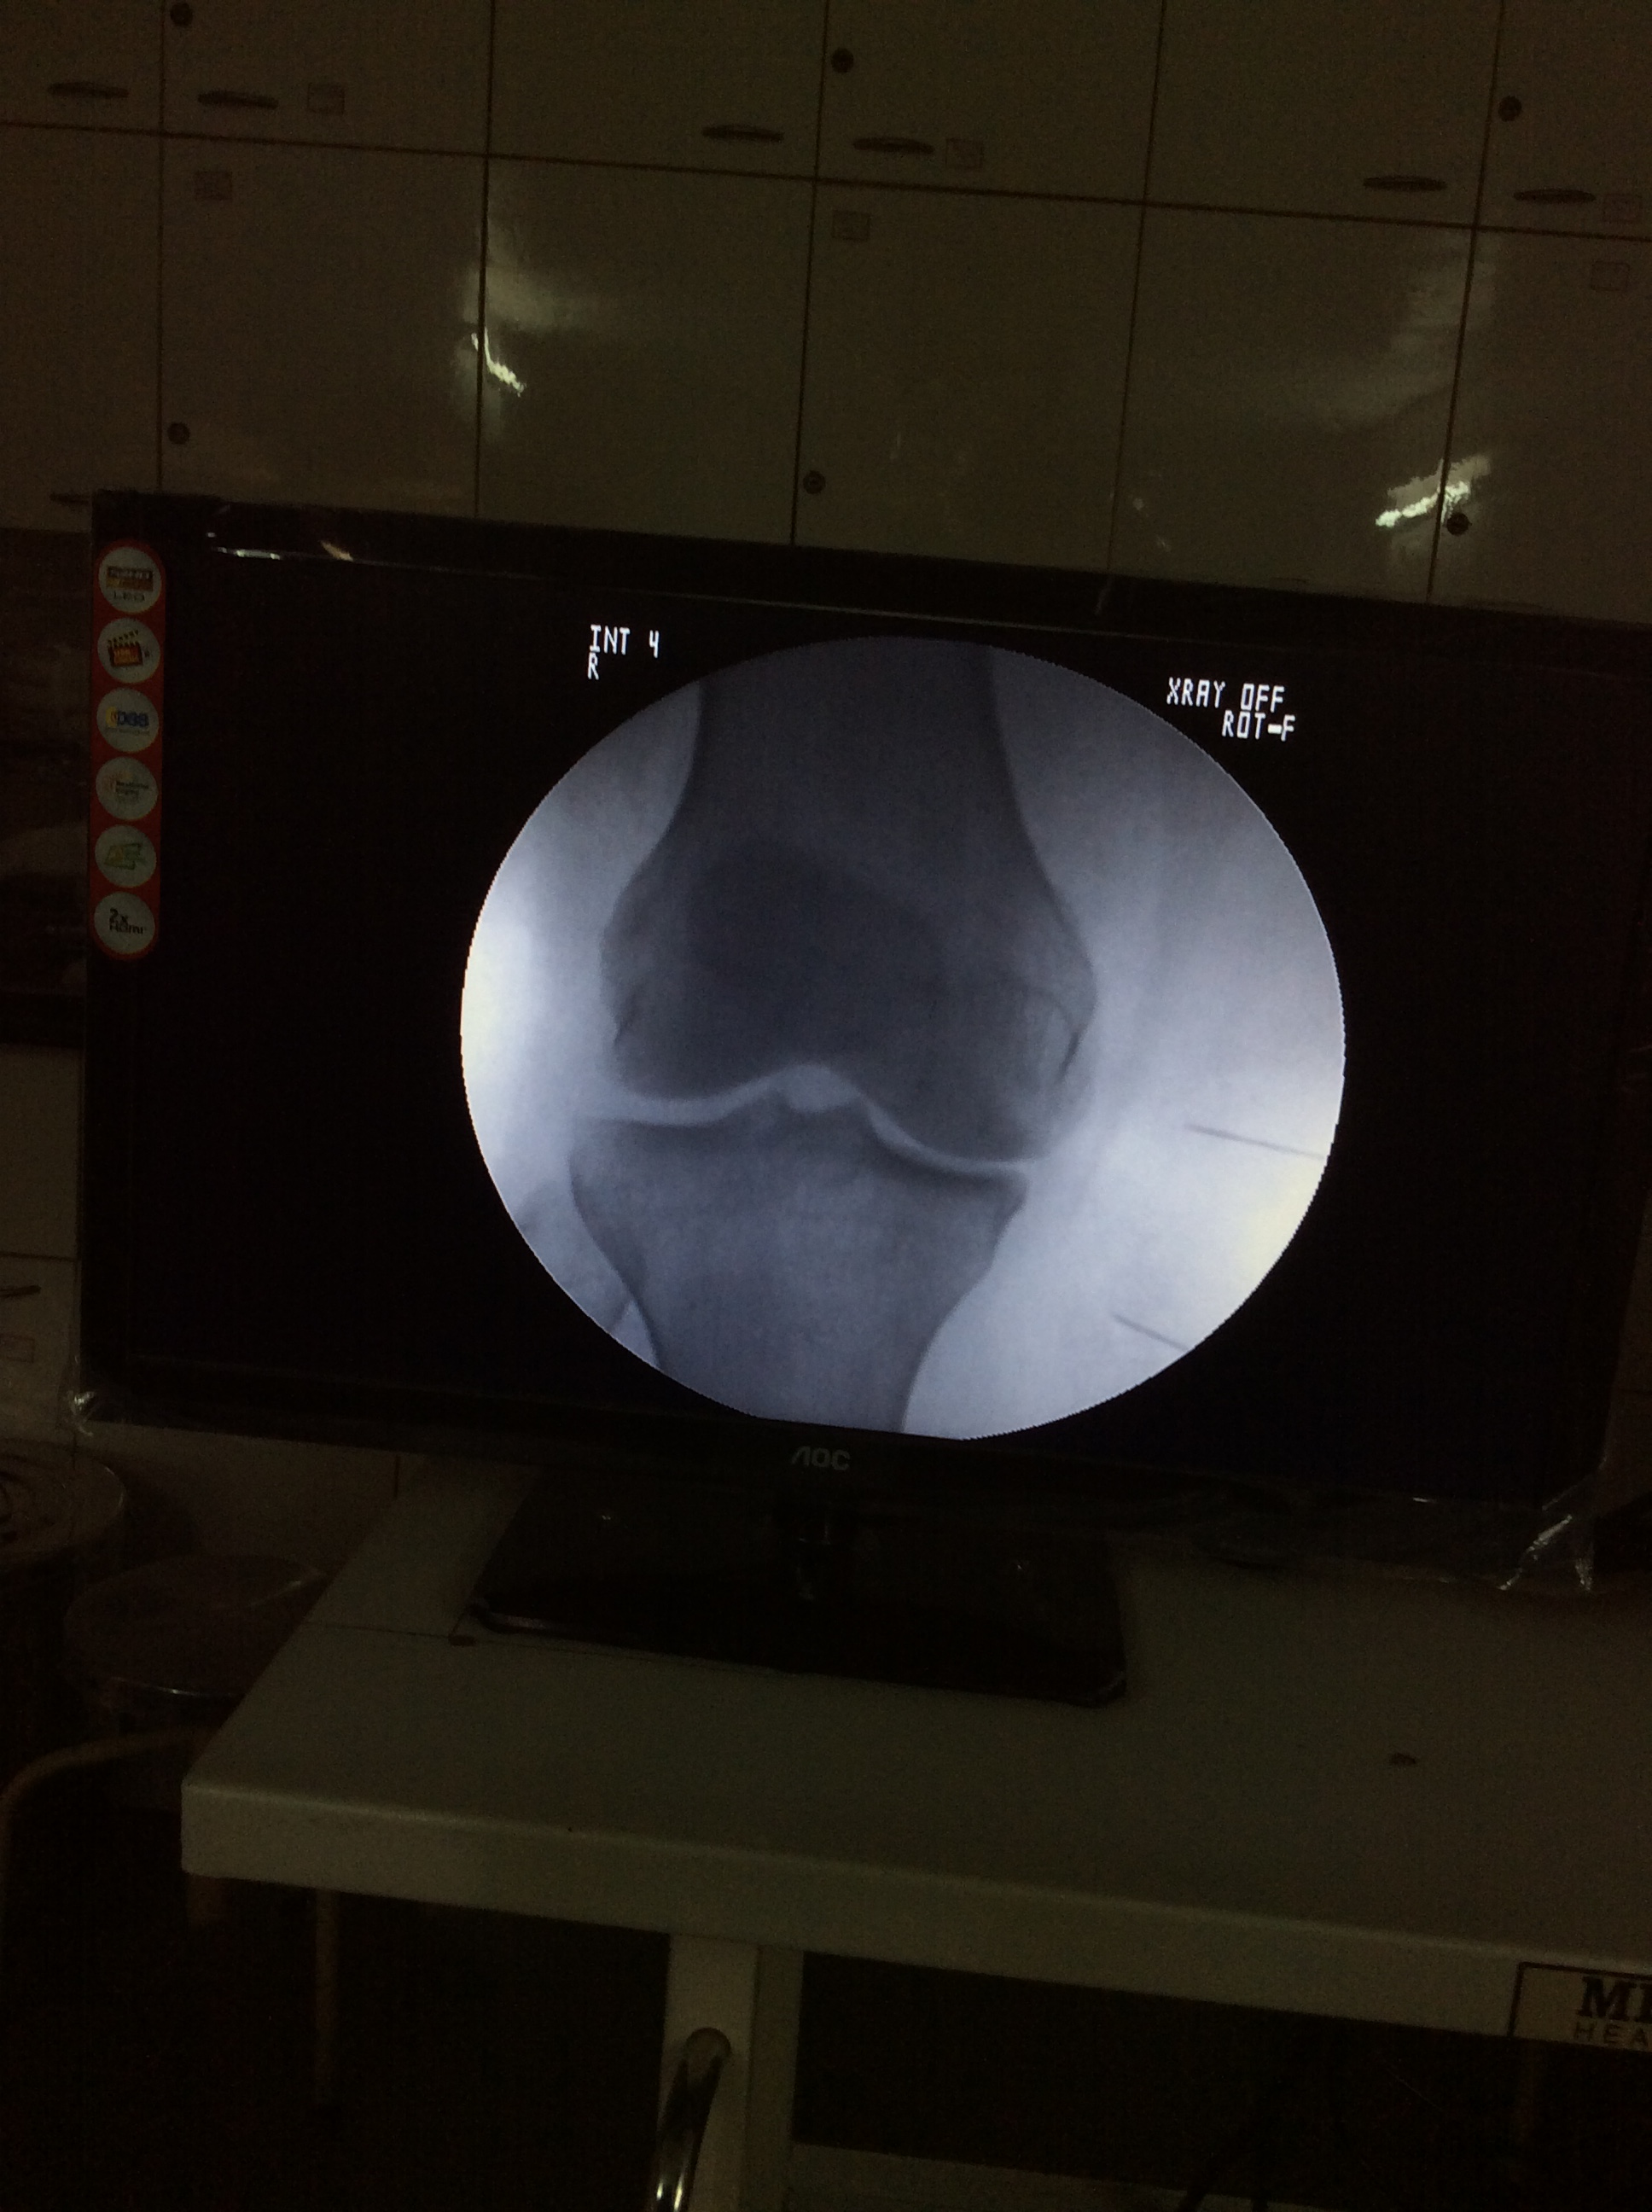

In radiofrequency neurotomy, the radio waves are delivered to the targeted nerves via needles inserted through the skin above your spine. Imaging scans are used during radiofrequency neurotomy to help the doctor position the needles precisely.

Genucular radiofrequency ablation for chronic knee arthritis pain

As with many spinal injections, radiofrequency neurotomy is best performed under fluoroscopy (live x-ray) for guidance in properly targeting and placing the needle (and for avoiding nerve injury or other injury). On the day of the injection, patients are advised to avoid driving and doing any strenuous activities. Patients may continue to take any normal medications except aspirin or any other blood-thinning medications, such as Coumadin.

- The physician uses x-ray guidance (fluoroscopy) to direct a special (radiofrequency) needle alongside the medial or lateral branch nerves.